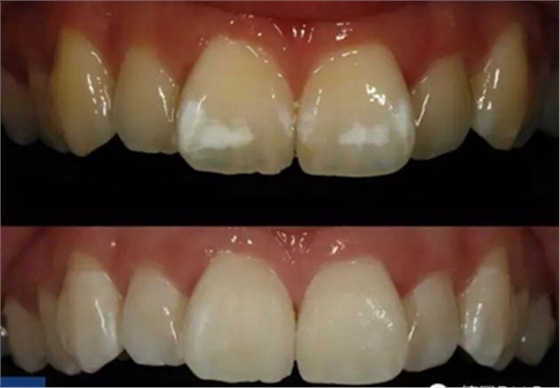

作為日常檢查的一部分,患者強(qiáng)烈要求對(duì)前牙區(qū)的白色斑塊進(jìn)行治療(Fig. 1). 權(quán)衡比較了多種治療方案后, 患者和我們共同選擇了滲透治療。

經(jīng)大量研究和證據(jù)表明,滲透治療是最適合用于牙正畸后由于牙釉質(zhì)脫礦造成的白斑病變。根據(jù)患者的居住地區(qū)和成長經(jīng)歷以及白斑的表現(xiàn)形式,我們將位于牙位11和21的唇面白斑診斷為氟牙癥指數(shù)0.5(根據(jù)Dean的社區(qū)氟牙癥指數(shù)).

經(jīng)拋光, 治療結(jié)果令人滿意并且印象深刻 (Fig. 7 and 8)。